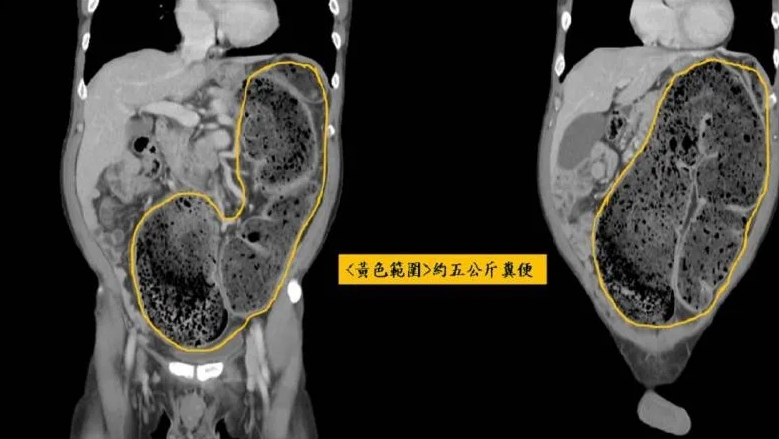

據了解,58歲男子經電腦斷層掃描,發現有異於常人約80公分的乙狀結腸,塞了約5公斤的宿便,一路頂到橫膈膜、胸腔,甚至還頂到心臟。大腸直腸外科醫師張巨成透露,該男子當時約有6*6公分的糞石,堵在大腸和乙狀結腸交接的地方,因此只能透過手指將糞石捏碎,花了約10分鐘將大糞石慢慢挖出來,而男子症狀也得到了緩解,回家排了十幾次便後,才將20天約5公斤的宿便排出。